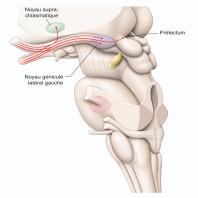

- eFig. 5-9 - Anatomie macroscopique de la voie rétino-prétectale et rétino-hypothalamique en coupe axiale passant par les noyaux géniculés latéraux en vue de profil gauche